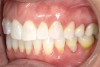

A 52-year-old female patient with history of lost retainers that she had used for a previous orthodontic treatment presented with minor orthodontic relapse during a hygiene visit. Her chief concern was that her lateral incisors were "starting to flare forward," as she had not been compliant with her retainers, and she expressed a desire for an affordable clear aligner solution. Clinically she presented with upper and lower anterior tooth crowding of less than 3 mm, specifically lower anterior teeth Nos. 23, 24, and 25, with a reverse curve of Spee of less than 2 mm on the lower anterior teeth (Figure 1 through Figure 3). The upper anterior arch presented with lateral incisor buccal rotations of less than 15 degrees on teeth Nos. 7 and 10 from an overjet view (Figure 4). The patient's oral hygiene was within normal limits, with stage one gingivitis, based on the new multidimensional staging and grading system of the American Academy of Periodontology and the European Federation of Periodontology that was adopted in 2017.12 The patient also presented with class I bite classification with gingival abfraction on both the anterior and posterior arches, with visibly missing class V restorations (Figure 5 and Figure 6).

Fig 1. Patient presented with upper and lower anterior tooth crowding

of less than 3 mm. Figure 1: Anterior view. Figure 2: Upper arch. Figure 3: Lower

arch.

Figure 1

Fig 2. Patient presented with upper and lower anterior tooth crowding

Figure 2